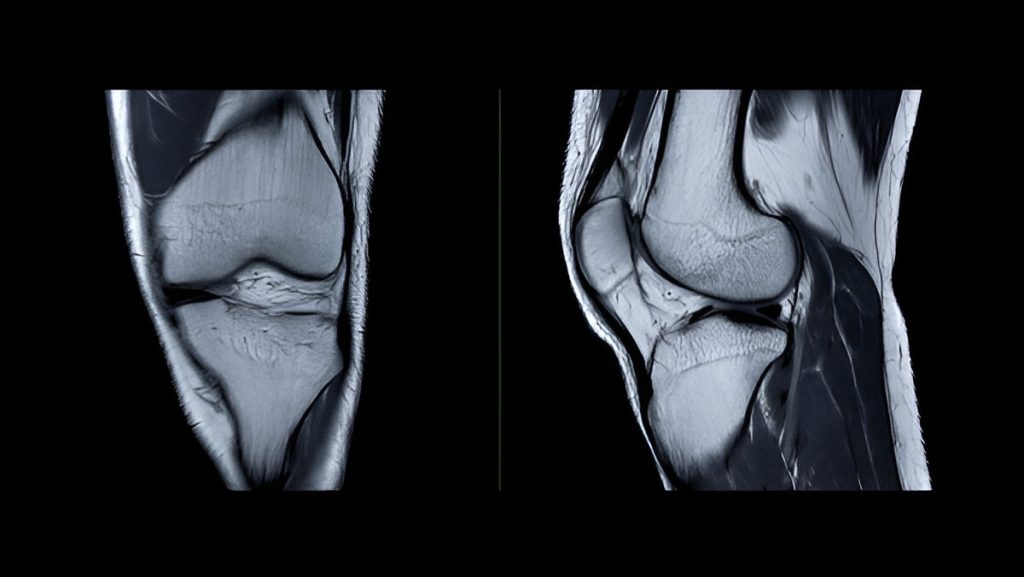

Understanding Knee Anatomy

The knee is one of the most powerful and intricate joints in the human body. It supports your weight, absorbs shock, and enables a wide range of motion. Whether you’re a professional athlete or just climbing stairs, your knees are constantly at work.

Cartilage: The Knee’s Cushion

Two types of cartilage provide support and shock absorption:

• Articular cartilage – Smooth tissue covering bone ends to reduce friction.

• Meniscus (Medial & Lateral) – C-shaped fibrocartilage acting as shock absorbers and stabilizers.